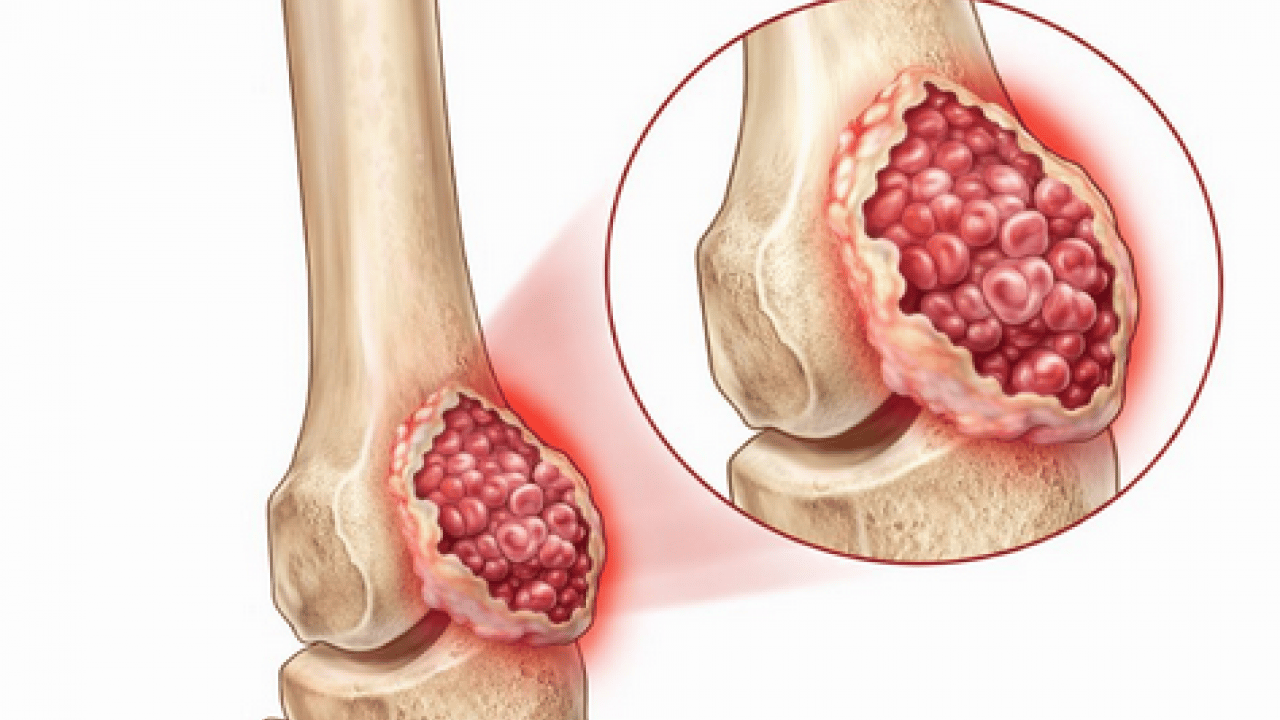

Tedavi sürecinin tümörün biyolojik yapısına, yerleşimine ve yayılım durumuna göre şekillendiğini kaydeden Doç. Dr. Ayas, iyi huylu tümörlerde genellikle daha sınırlı ve koruyucu cerrahi müdahalelerin yeterli olabildiğini söyledi. Kötü huylu tümörlerde ise tümörün yalnızca görünen kısmının değil, çevresindeki potansiyel riskli dokularla birlikte çıkarılmasının hayati önem taşıdığını ifade etti. Bu yaklaşımın, hastalığın tekrar etme riskini azaltarak uzun dönem tedavi başarısını artırdığını dile getirdi.

Cerrahi tedavinin, hastalığın türü, hastalığın evresi ve hastaya özgü klinik özelliklere göre kemoterapi ve radyoterapi ile desteklenebildiğini aktaran Doç. Dr. Muhammet Salih Ayas, tanı sürecinde ileri görüntüleme teknikleri ve biyopsi uygulamalarının büyük bir titizlikle yürütüldüğünü belirtti.

Doğru tanının, tedavi planlamasının en kritik aşamalarından biri olduğuna dikkat çekti.

Ameliyat sonrası oluşan kemik ve doku kayıplarının modern rekonstrüksiyon yöntemleriyle başarıyla giderilebildiğini ifade eden Ayas, "Biyolojik teknikler, hastaya özel geliştirilen protezler ve kemik transferleri sayesinde hem anatomik bütünlüğü yeniden sağlıyor hem de hastalarımızın fonksiyonlarını en iyi şekilde korumayı hedefliyoruz" diye konuştu.